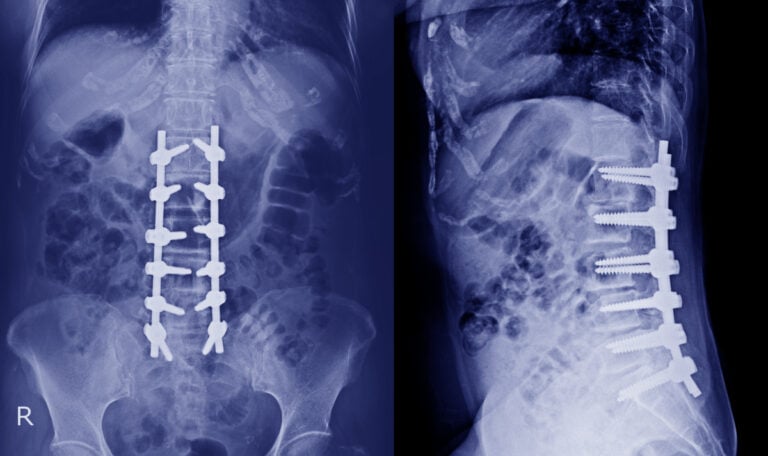

Minimally Invasive Spine Surgery

Minimally Invasive Spine Surgery in Bangalore

In recent years, Minimally Invasive Spine Surgery in Bangalore has revolutionized the way spinal conditions are treated. For patients struggling with chronic back pain, herniated

Spine Surgery

Common Myths and Facts About Spine Surgery

Back pain is one of the most common health complaints in India, and spine surgery often emerges as a solution when conservative treatments fail. However,